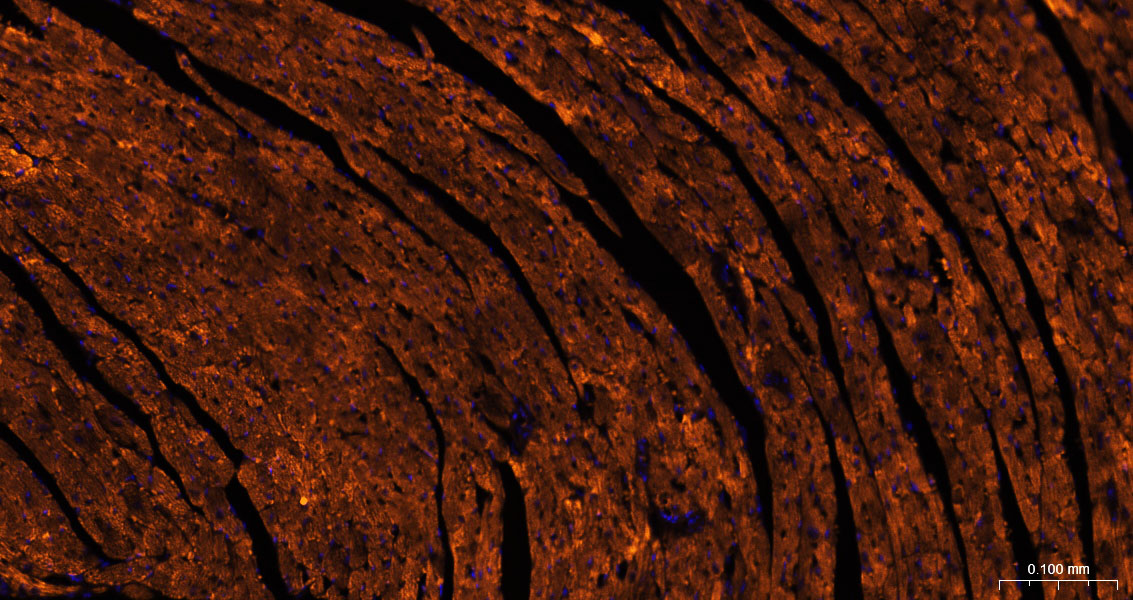

COX4I1 Monoclonal Antibody, Cy3 Conjugated

Product Name COX4I1 Monoclonal Antibody, Cy3 Conjugated

Conjugation Cy3

Synonyms Cytochrome c oxidase subunit 4 isoform 1, mitochondrial; COX4I1

Background This protein is one of the nuclear-coded polypeptide chains of cytochrome c oxidase, the terminal oxidase in mitochondrial electron transport.